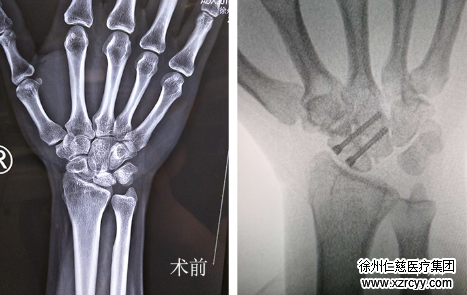

>>>>病情:患者,男,42岁,半年前右腕出现疼痛,后来右腕部又相继出现活动受限,背伸、屈曲,桡偏疼痛加剧。

由于患者此前没有进行任何治疗,疼痛逐日加剧,为寻求进一步治疗特来我院。诊断发现,患者右腕月骨坏死,需手术进行摘除。经北京大学医学博士、北京积水潭医院手外科主任医师刘波教授、我院手外二病区专家团队研究决定,行关节镜下右腕月骨摘除+部分关节融合术。

术中,在关节镜下探查并取出坏死月骨,磨钻打磨舟骨关节面,融合舟头关节,术后患者右腕疼痛消失,活动功能得到最大程度恢复,效果满意。